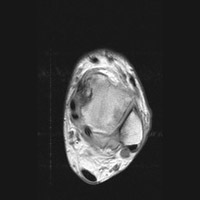

C C | Axial MRI. This proton density image of the ankle demonstrates a region of intermediate signal intensity at the lateral aspect, corresponding to edema. |